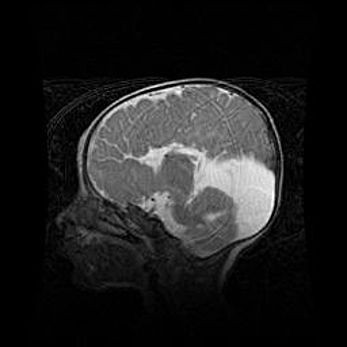

Лейкомаляция с кистозно-глиозной дегенерацией головного мозга.

Возраст: 2 месяца 25 дней

Вес: 6400 г

Окружность головы: 40 см

Срок гестации: 41 неделя

Лейкомаляцию относят к ишемически-гипоксическим повреждениям головного мозга, диагностируемым у новорожденных. При лейкомаляции в головном мозге обнаруживают очаги некроза, возникшие после тяжелой гипоксии и нарушения кровотока. В процессе морфогенеза очаги проходят три стадии: 1) развития некроза, 2) резорбции и 3) формирования глиозного рубца или кисты. Перивентрикулярная лейкомаляция (ПЛ) встречается примерно в 12% случаев среди новорожденных, обычно – у недоношенных детей, причем, частота ее зависит от массы, с которой младенец появился на свет. Наибольшее число малышей страдает лейкомаляцией, если масса при рождении 1500-2500 г.